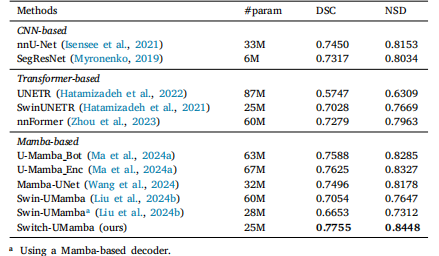

Table 1Results of organ segmentation on the Abdomen MRI dataset. For a faircomparison, the Swin-UMamba results are reported without the benefit ofImageNet-based pre-training

表1 腹部MRI数据集上的器官分割结果 为保证对比的公平性,所报告的Swin-UMamba模型结果未借助基于ImageNet的预训练(优势)。